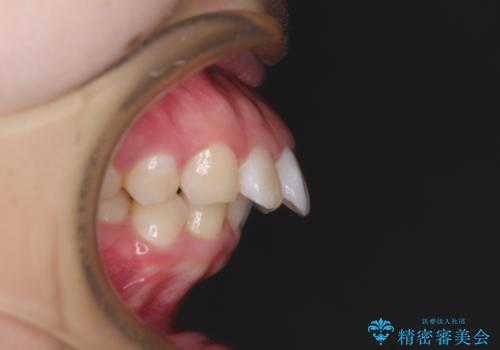

くちばしのように前歯が突出していたため、口元を積極的に引っ込めるために、上下左右の小臼歯4本を抜歯することとしました。

また、上顎歯列が下顎に対して前方位に位置していたため、補助装置を用いて上顎歯列を後方に移動させ、より積極的に口元を下げるようにしました。